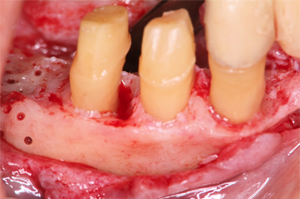

残存した歯を利用して可能な限り固定式のブリッジで対応できるよう歯周組織の再生を図りました。(再生療法)

抜歯した部位に

再生療法を実施

縫合

抜歯と歯周外科処置

上顎前歯部は保存不可能な歯の抜歯と歯周外科処置を行うことでブリッジが長持ちできるように歯周環境を整えました。

残存した歯を利用して可能な限り固定式のブリッジで対応できるよう歯周組織の再生を図りました。(再生療法)